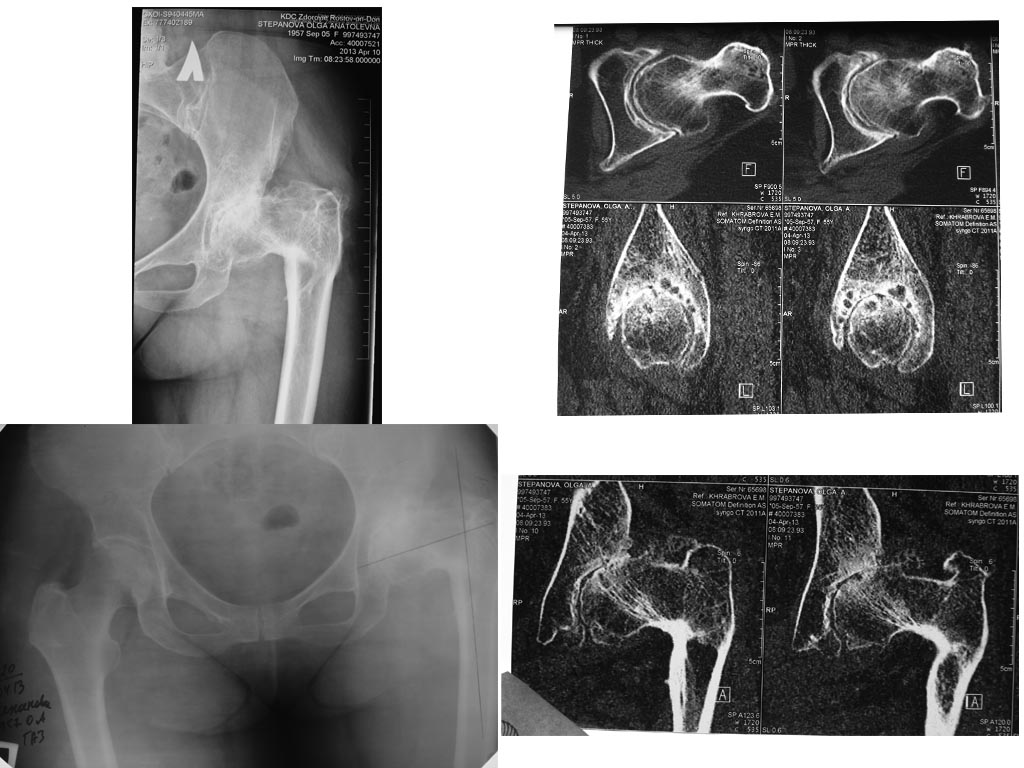

Даме 56 лет. В 11 лет ей была выполнена  варизирующая остеотомия

проксимального отдела бедра в связи с дисплазией левого тазобедренного

сустава.

В настоящее время:

Жалобы на боль (5 баллов по ВАШ), ограничение движений в левом т/б

суставе (обективно: сгибание до 150 град, отведение 20 град, ротация

20), укорочение (приблизительно 8 см). Желает эндопротезирование.

Предложение: для начала выполнить удлинение "на гвозде" на 4-5 см

(остеотомия на уровне дистальной трети), затем - говорить об

эндопротезировании.

Обоснование: 1) удлинить при эндопротезировании на 8 см не

представляется возможным из-за ригидности мышц и сухожилий; 2) высокой

вероятности вывиха эндопротеза после осуществления релиза тазобедренного

сустава; 3)вероятность тракционного повреждения седалищного нерва.